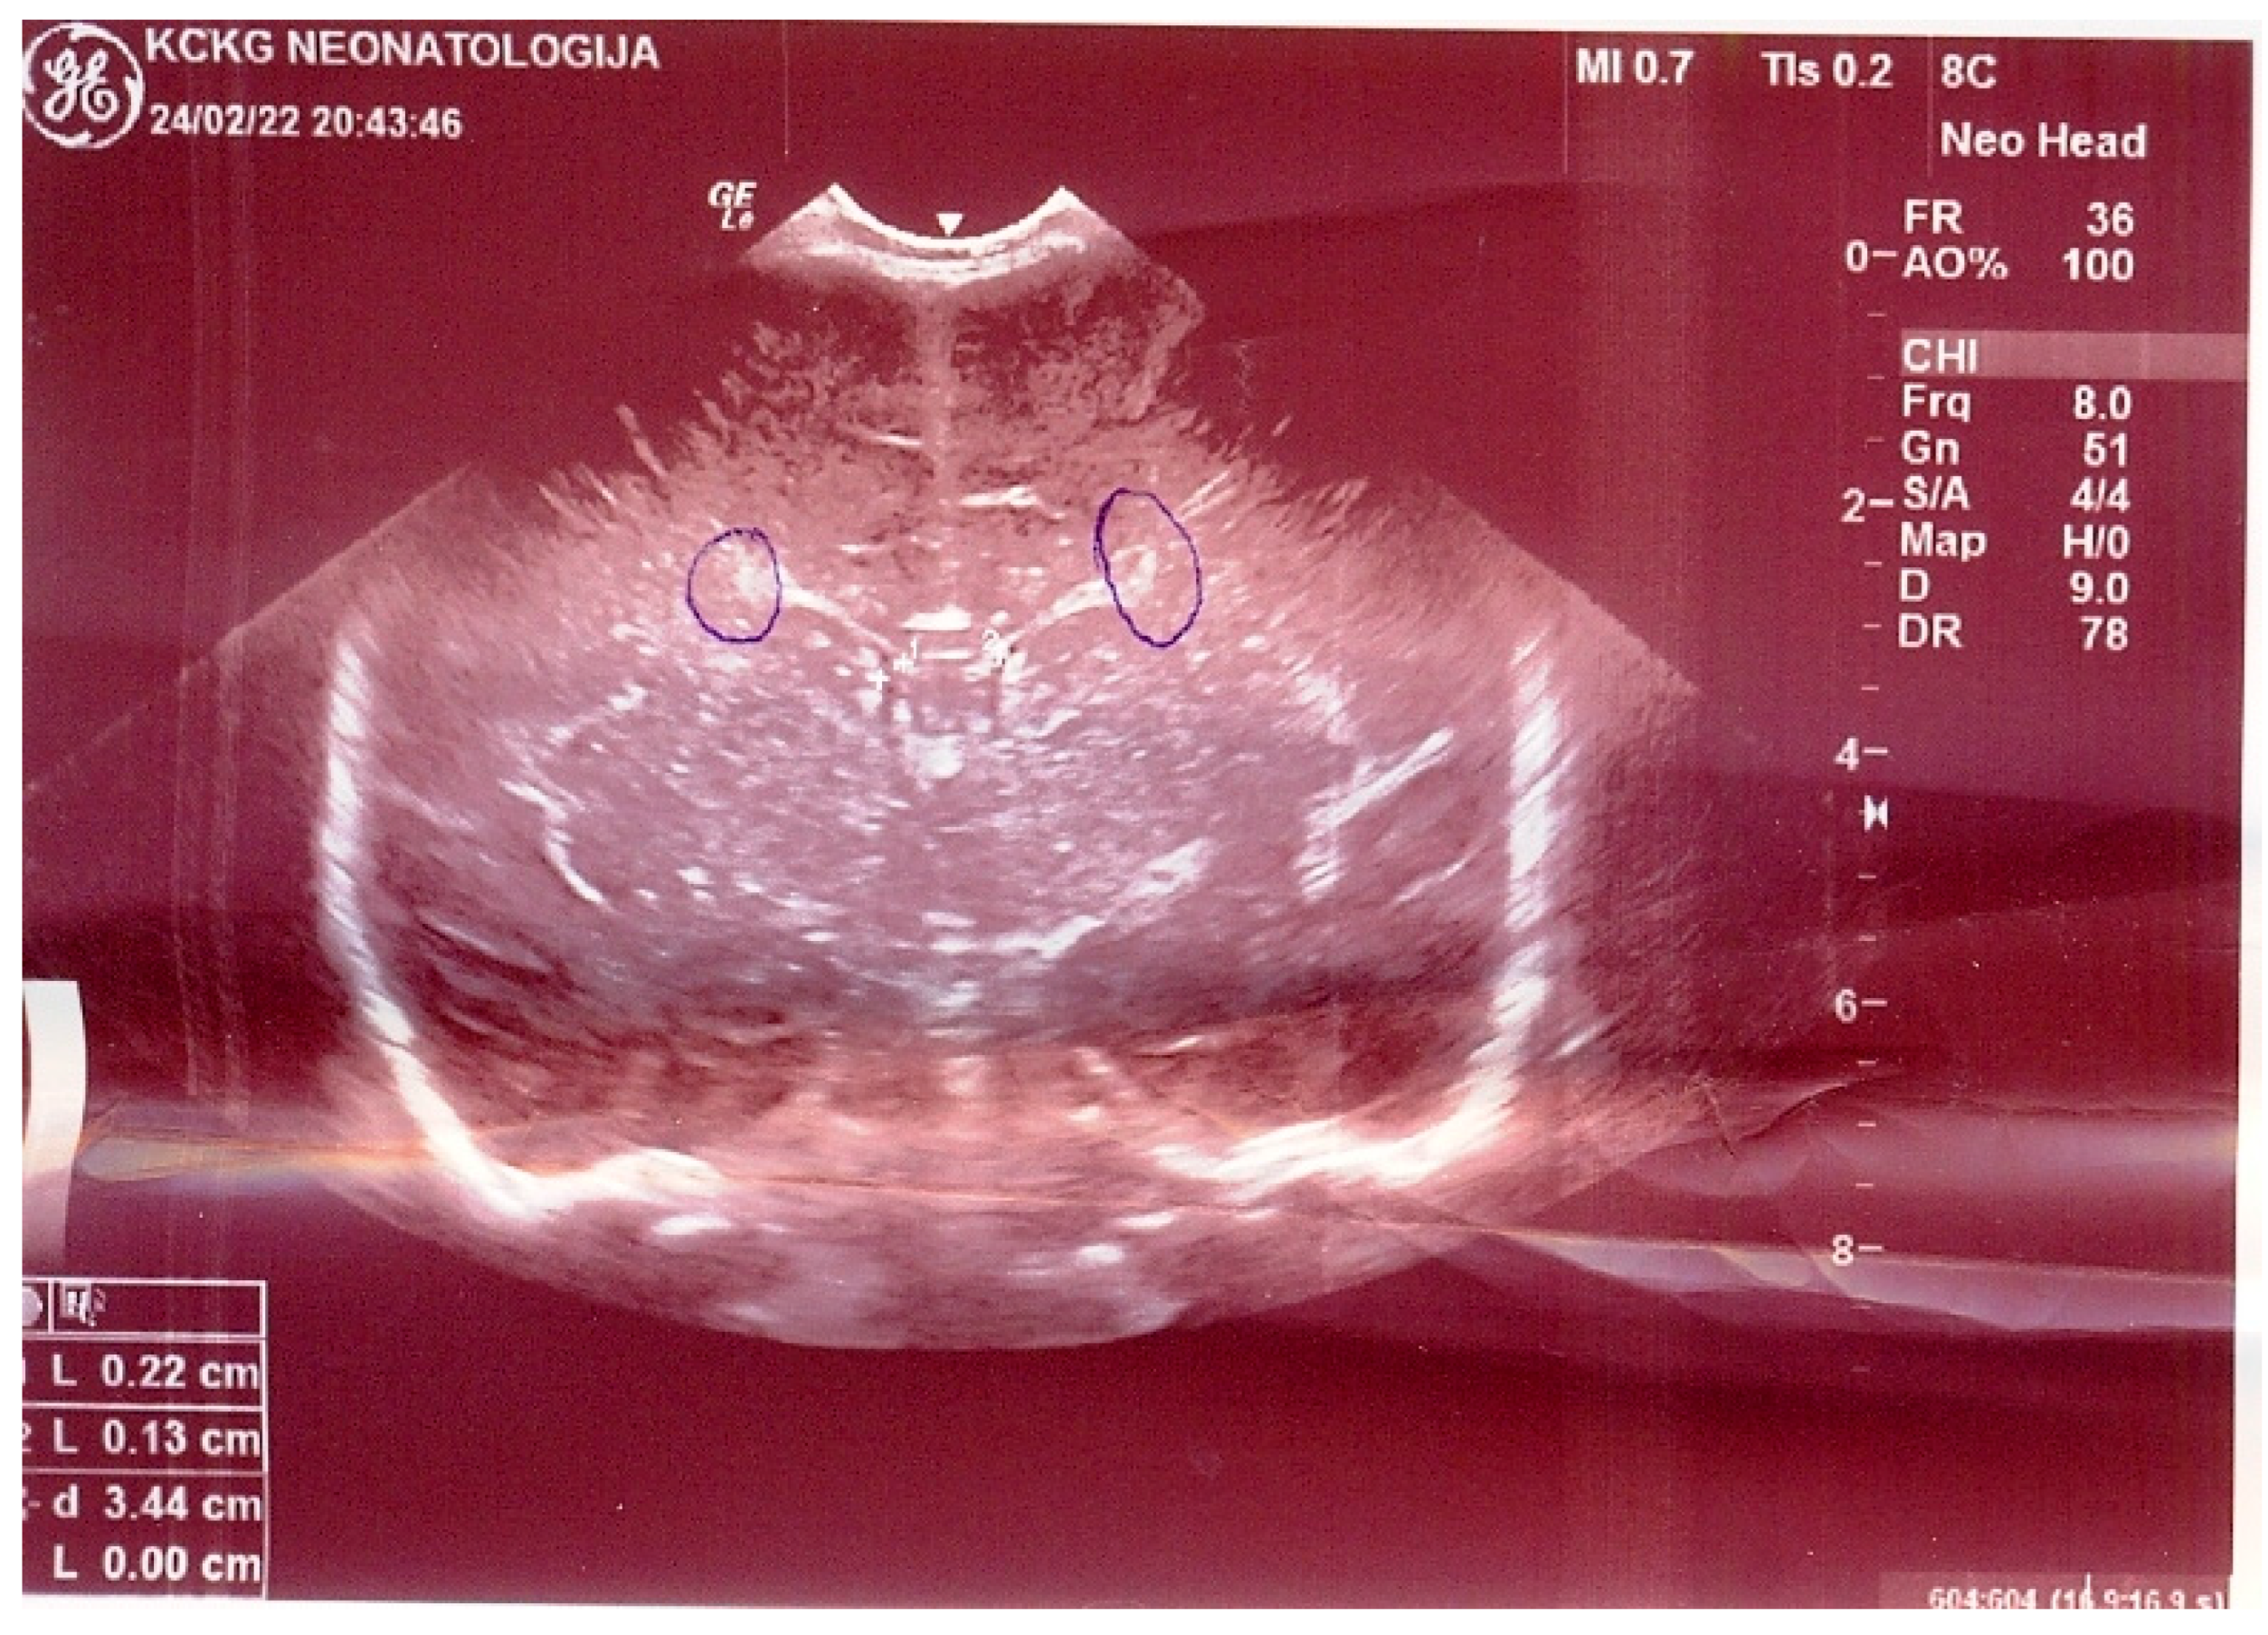

| Clinical picture at admission in Pediatric Clinic UCC | NN1 had a preserved sensorium, was high febrile 39.4 °C (rectal), with tachy-dyspnea, sobs, and moans, indents jugulum, dissatisfied cries, TM 4050 g, subclinical jaundice of the skin, and visible mucosa. Auscultation revealed attenuated respiratory sound, diffusely fine crackles, SaO2 82%, R 56/min, F 196/min. The umbilical stump persisted, the surrounding skin became red and swollen, there was hypotonia of the body axis, large fontanelle within the bony borders, greatness 20 × 30 mm. The other physical findings were normal. | NN2 had the preserved sensorium, was afebrile 37.7 °C (rectal), TM 3920 g, eupnoeic, presented sobs and moans, plethoric and icteric skin, nasal vestibules filled with seromucous secretion, and hyperemic throat. Auscultatory revealed a normal breathing sound is heard with transmitted wheezes from the upper parts of the airways and systolic murmur of 1-2/6 according to Levin, SaO2 97%, R 32/min, F 168/min. The umbilical stump persisted, thin, and the borders developed a serous–hemorrhagic discharge. There was mild hypotonia of the shoulder girdle and trunk axis, primitive reflexes were slowly elicited, large fontanelle was below the plane of the bony borders, and slightly spaced sutures, greatness 40 × 40 mm. The other physical findings were normal. |

| Tracheal aspirate by RT-PCR testing | Legionella pneumophila serogroup 2-15 | Legionella pneumophila serogroup 2-15 | |

| Culture of tracheal aspirate on the GVPC nutrient media | Legionella pneumophila, Pseudomanas aeriginosa | Legionella pneumophila | |